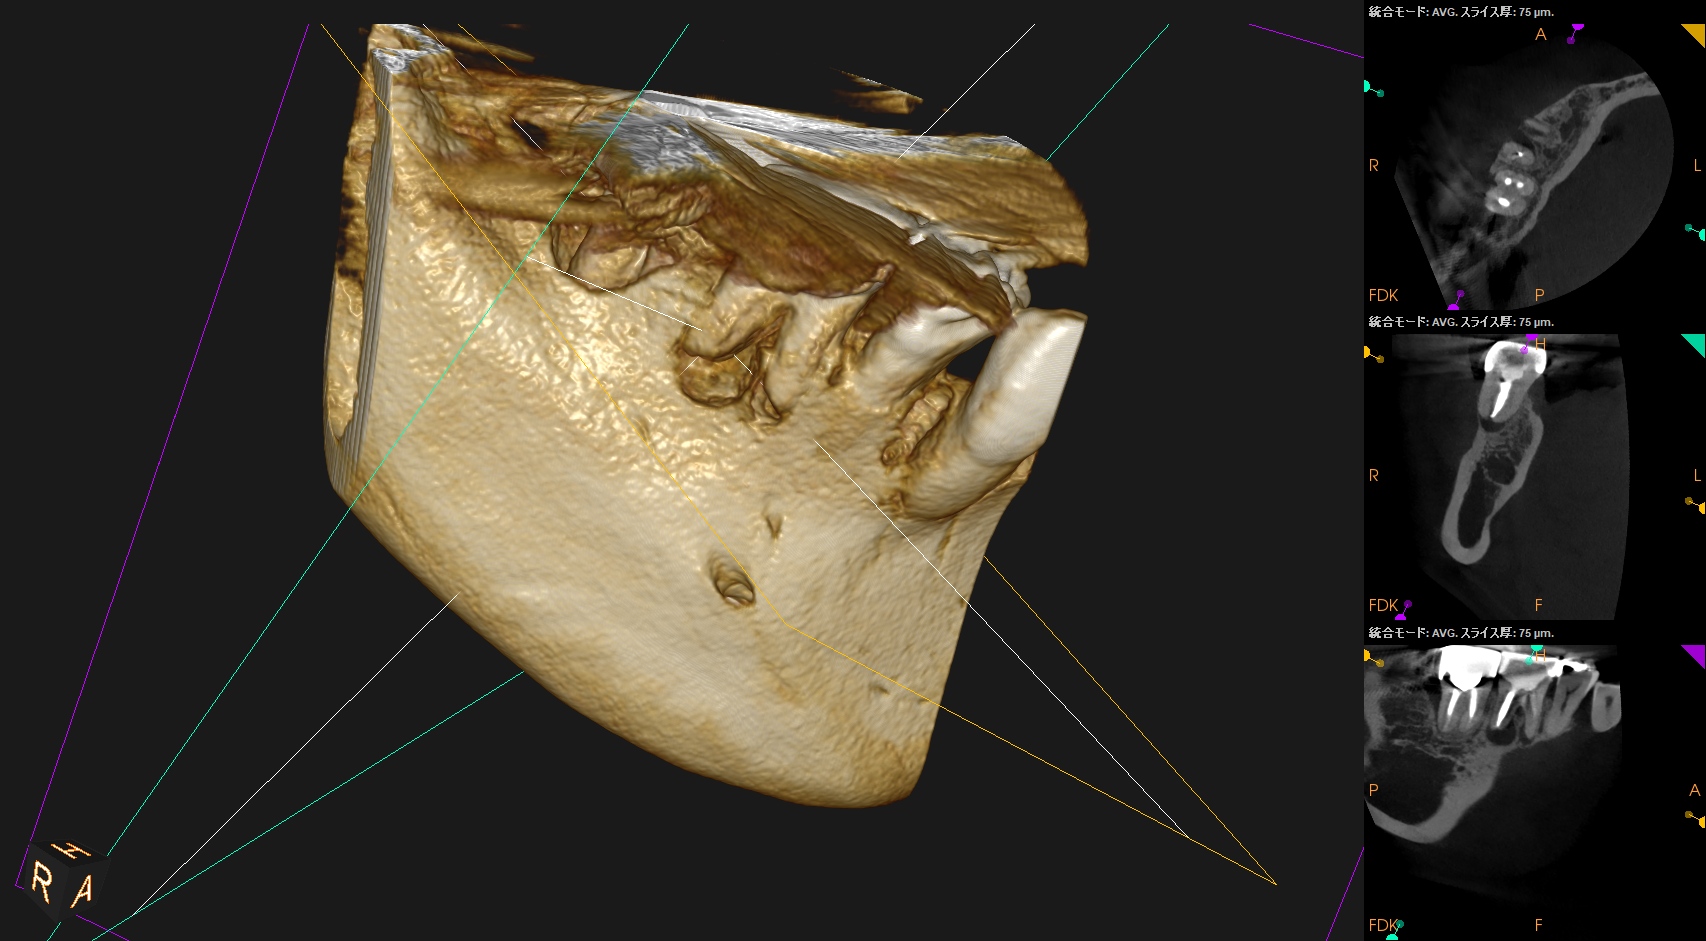

術後にPA, CBCTを撮影した。

#30

MB

ML

D